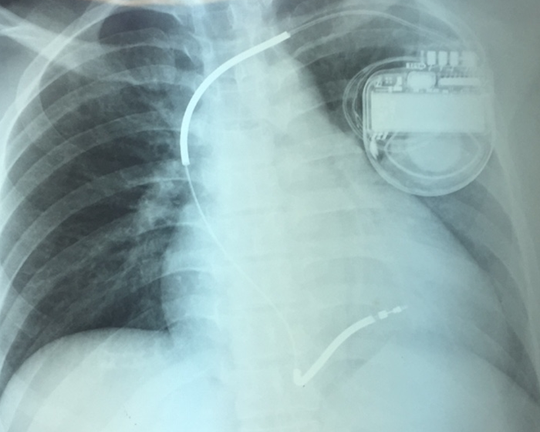

Một người phụ nữ trẻ mắc bệnh yếu cơ tim gây rối loạn nhịp tim hiếm gặp, có thể đột tử bất cứ lúc nào vừa được các bác sĩ Bệnh viện Chợ Rẫy cứu chữa.